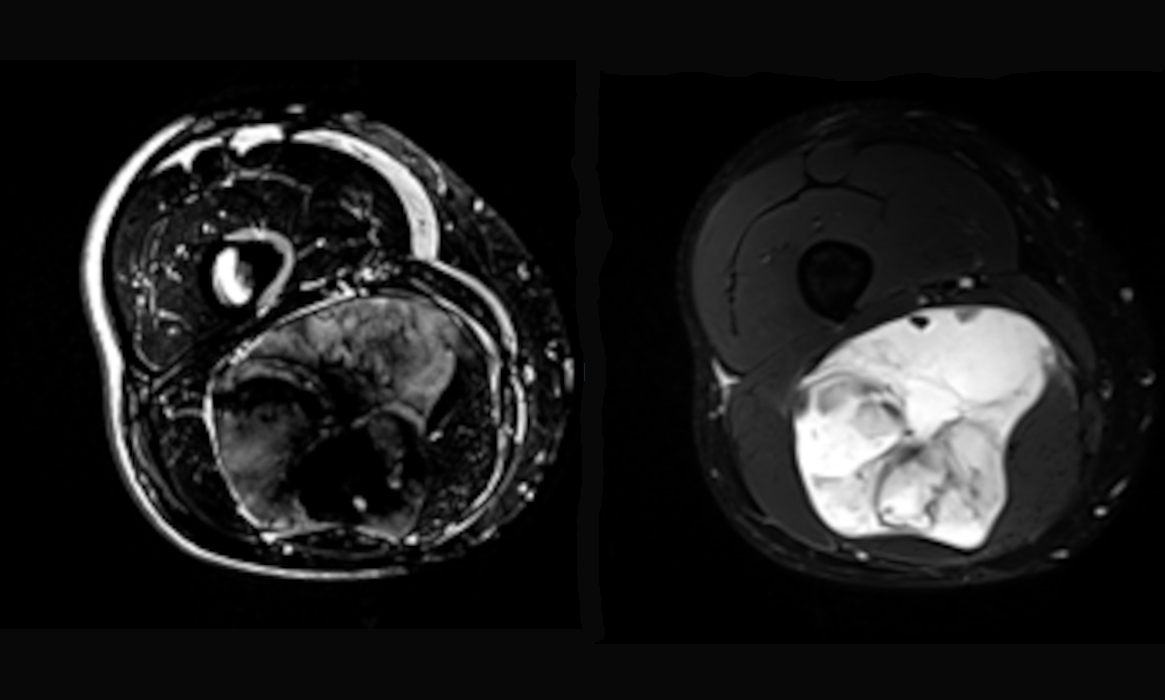

Notre objectif est de développer de nouvelles méthodes de mesure des paramètres indirects basés sur l'IRM et l'optique, ainsi que de rechercher de nouveaux biomarqueurs de manière rapide, robuste, reproductible et fiable, tout en prenant en compte les mouvements physiologiques. Les biomarqueurs recherchés proviennent des propriétés mécaniques, biochimiques ou structurelles des tissus étudiés. Nous aspirons à combiner les innovations basées sur la physique à l'origine de la création d'informations mécaniques, biochimiques ou structurelles, tant du point de vue des stratégies d'acquisition que de l'instrumentation, et à ancrer ces développements dans la pratique clinique.